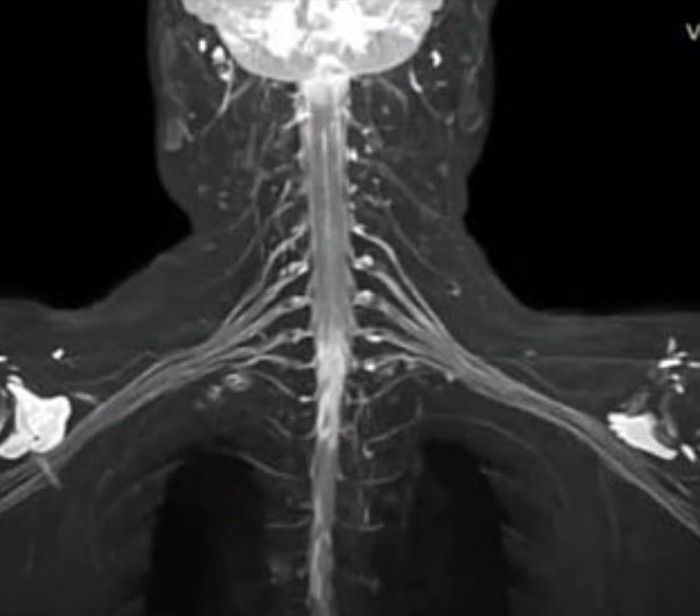

The brachial plexus is a network of nerves in the shoulder that carries movement and sensory signals from the spinal cord to the arms and hands. Injuries of Brachial plexus typically stem from trauma to the neck, and can cause pain, weakness and numbness in the arm and hand. By:https://www.instagram.com/p/CRmpPwEjdGo/?utm_medium=copy_link